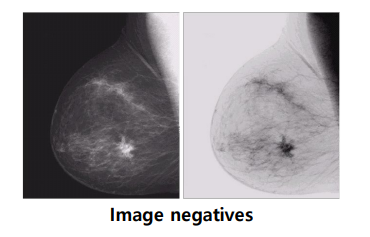

Gray-Level Slicing

특정한 Pixel Value 영역을 기준으로 밝기값을 조절하는 영상 처리 기법이다.

첫번째 그래프는 $A,B$를 제외한 모든 영역의 밝기 값을 0에 가까운 값으로 설정함을 알 수 있다.

반면, 두번째 그래프는 $A,B$를 제외한 모든 영역의 밝기는 유지하면서, 해당 영역은 원본보다 더 밝은 값으로 설정함을 알 수 있다.

우리가 추출하기 원하는 영역, 대상의 밝기 값 분포를 알고 있다면, 해당 영역 제외 모두 0으로 설정하여 원하는 영역만 확인할 수 있다.